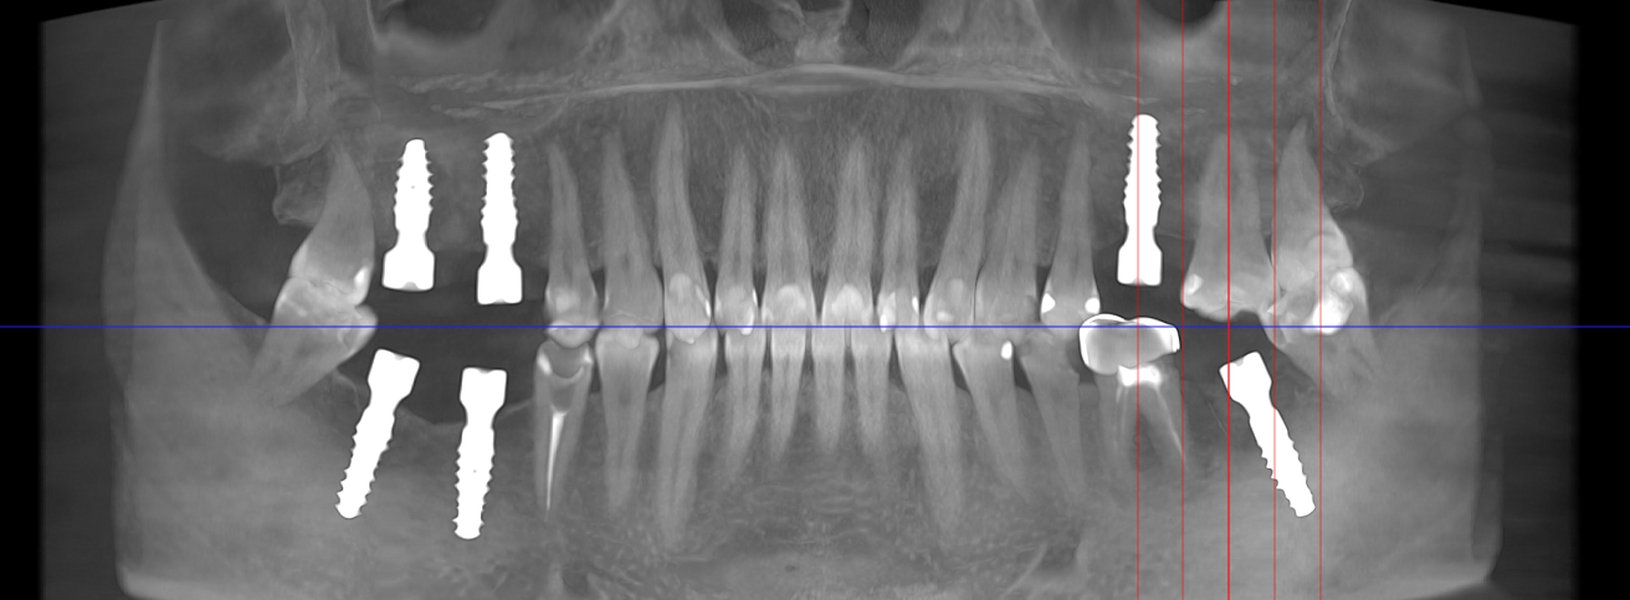

- Consultația inițială și planificarea tratamentului (inclusiv tomografie CBCT)

- Inserarea implanturilor dentare (chirurgie ghidată digital)

- Realizarea lucrării protetice (coroană, punte sau proteză)

- Fixarea lucrării și verificarea ocluziei

- Proteze pe sistem de bare sau capse (All-on-4, All-on-6)

- Tehnologie digitală de ultimă generație – scanare 3D, design asistat digital

- Chirurgie implantologică ghidată, minim invazivă